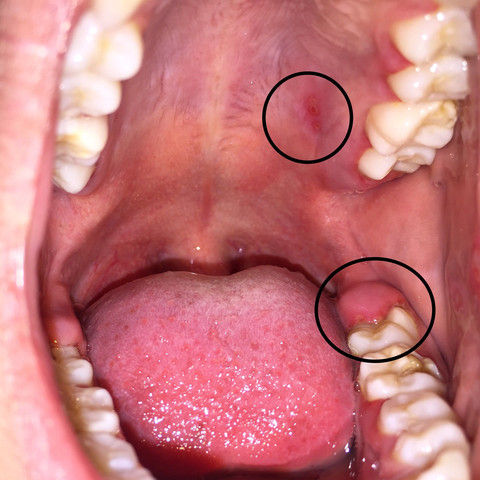

Auch Gurgeln ist ein beliebtes Hausmittel bei Halsschmerzen. Wie bekomme ich Halsschmerzen so schnell wie möglich weg. Ist eine bakterielle Tonsillitis also eine Mandelentzündung diagnostiziert wird ein Arzt in vielen Fällen ein Antibiotikum verschreiben das die verantwortlichen Bakterien abtötet.